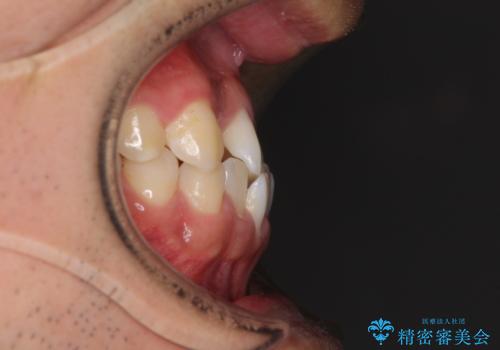

- 前歯のクロスバイトを気にして来院された患者様です。

美容専門の歯科医院を受診したところ、セラミックでの改善は無理と断られてしまったとのことでした。

歯がすり減って不揃いの形態となっていますが、まずは矯正治療によりクロスバイトを改善することとしました。

治療期間を極力短くしたいとのことで、ワイヤー矯正により治療を行うこととしました。